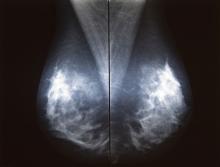

The outlook of breast cancer is changing, and death rates have been decreasing since 1989, thanks in part to treatment advances, earlier detection through screening and increased awareness.

The digital breast tomosynthesis (DBT) market has evolved rapidly within the past year, with new vendors entering the market and recent clinical data continuing to support its use. In addition, the Centers for Medicare and Medicaid Services (CMS) created dedicated reimbursement codes for DBT procedures earlier this year.